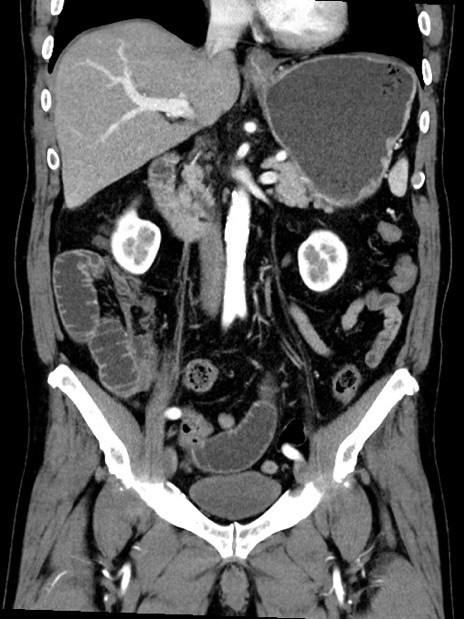

横断像

症例35(冠状断像)

【症例】70歳代 男性

【主訴】腹部膨満、嘔吐

【現病歴】昨日より腹部膨満感出現。本日増悪し、仙痛出現。嘔吐あり、受診。

【既往歴】糖尿病、胆摘後

【身体所見】BP 149/80mmHg、HR 74/min、BT 35.9℃、腹部:膨満、軟、圧痛なし。腸雑音減弱あり。上腹部正中切開瘢痕あり。

【データ】WBC 13500、CRP 1.72